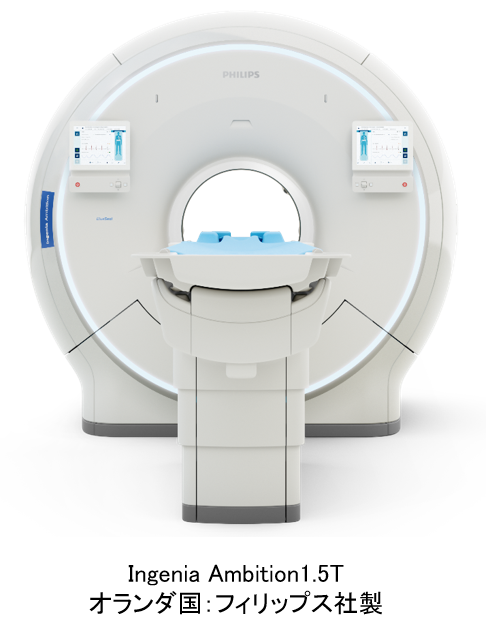

医療関係者向け個人被ばく線量の情報提供に関して(他施設様向け)